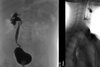

Cálculo da Idade pela Ossificação do Punho

Vincente Gilsanz e Osman Ratib